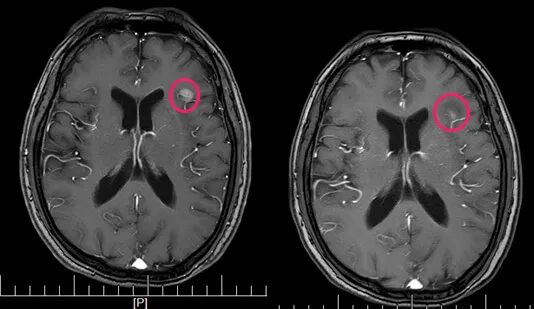

原本已稳定1年的颅内孤立转移灶

在逐渐长大

从1cm长到了1.8cm

做了头部病灶的立体定向放疗2次

后定期复查

颅内病灶逐渐在缩小

▲治疗前